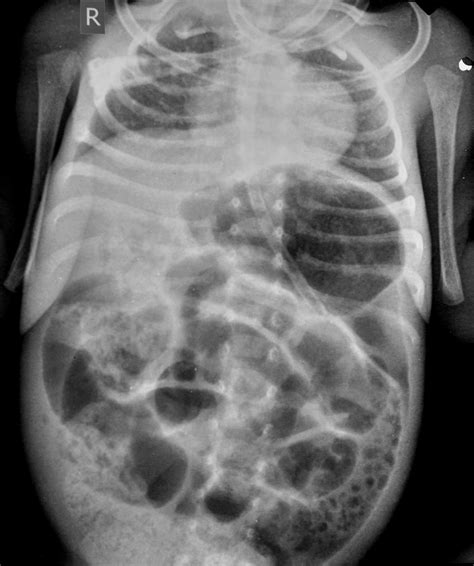

Soap Bubble Sign. A high index of suspicion is needed in preterm babies. An expansile lytic lesion with internal trabeculations and preserved cortex, usually of benign nature but may be used to describe more aggressive lesions.

Web check out our soap bubble poster selection for the very best in unique or custom, handmade pieces from our bar soaps shops. Early recognition of this finding and timely prompt intervention can significantly reduce mortality and morbidity. Web soap bubbles icon on white background. Web soap bubble appearance is an important classical radiological finding in neonatal necrotising enterocolitis. Web download over 2,137 icons of soap bubbles in svg, psd, png, eps format or as web fonts. Web check out our soap bubbles sign selection for the very best in unique or custom, handmade pieces from our shops. Web bathtub cat retro metal tin sign, black cat soak your troubles bubble bath soap foam poster vintage toilet cave bar home bathroom wall decoration sign 8x12 inches 4.7 out of 5 stars 49 save 39% A soap bubble appearance of a bone lesion refers to: Privacy settings etsy uses cookies and similar. A high index of suspicion is needed in preterm babies.